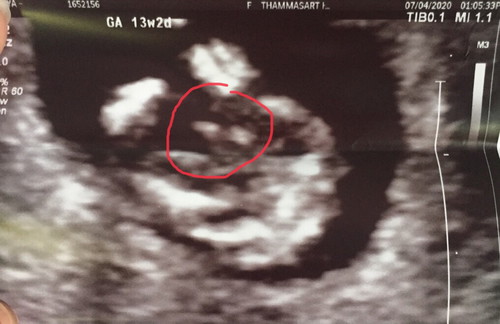

ภาพอัลตร้าซาวน์ที่วงกลมส่วนนี้ คือภาพอวัยวะเพศลูกหรือเปล่าคะ. คือส่วนไหนคะ ใครรู้บอกทีค่ะ

ใช่ค่ะ ยินดีด้วยค่ะแม่ใด้ลูกชายค่ะ

น้องมีจู๋คะคุณแม่😁